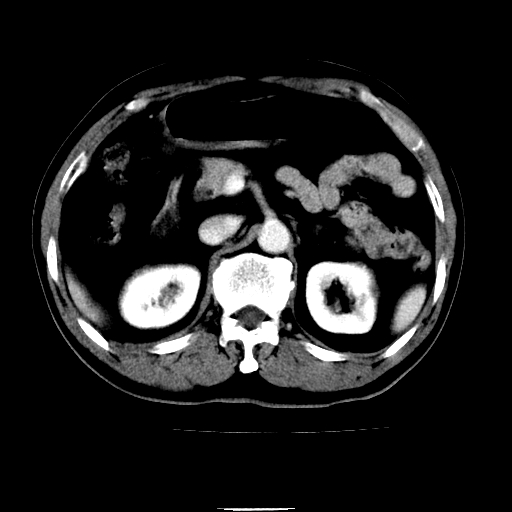

以下是引用chenqiong在2010-3-25 20:56:00的发言:[br]1、胆囊炎,胆囊息肉[br]2、肝内胆管及胆总管扩张,胆总管下端结石[br]3、十二指肠乳头旁憩室

以下是引用zxl51642在2010-3-26 10:47:00的发言:[br]胆囊炎,胆囊息肉,胆总管扩张,但未看到明显肿块,肝内胆管扩张不像恶性,炎性狭窄或阴性结石可能吧,建议mrcp,右肾小囊肿